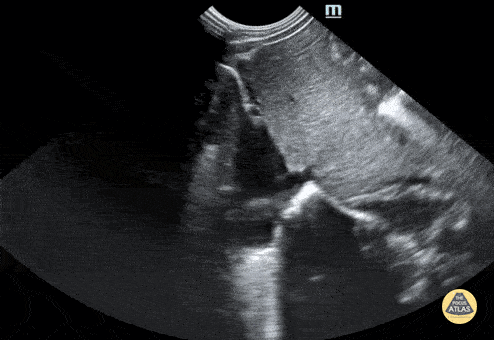

Normal neonatal IVC. Contributor: Jaron Smith, MD, Phoenix Children's Hospital

View: Unspecified Parasternal Long Axis Parasternal Short Axis Apical Four-Chamber Subcostal Four-Chamber Subcostal Inferior Vena Cava Right Upper Quadrant Left Upper Quadrant Suprapubic Longitudinal Suprapubic Transverse Subxiphoid Anterior Thoracic Phrenic